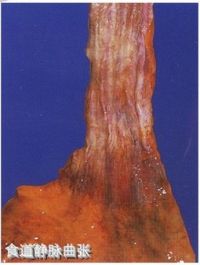

食管胃底静脉曲张

食道胃底静脉曲张是门静脉高压的主要临床表现之一,而导致门静脉高压最常见的病因是肝硬化。肝硬化病人中有40%出现食管胃底静脉曲张,而有食管胃底静脉曲张的病人中约有50%~60%并发大出血,其突出特点为出血量较大、来势迅猛、病情凶险、病死率高达40%以上,如不及时治疗,患者可因急性大出血发生失血性休克而导致严重后果。

在腹腔及腹腔邻近的一些组织或器官的静脉回流是直接进入下腔静脉回到心脏,这些静脉与胃肠的一些静脉之间的静脉存在交通支(即两者之间有血管相通)。这些交通支包括:食管与胃底静脉之间,直肠与肛门之间,胃肠道与后腹膜及肾之间等。当门脉高压时,上述交通支广泛开放和增加,原来已经闭塞的脐静脉也开放并通过腹壁静脉回流等。由于交通支的开放和增生,血流增加,使食管下段及胃底的静脉曲张。